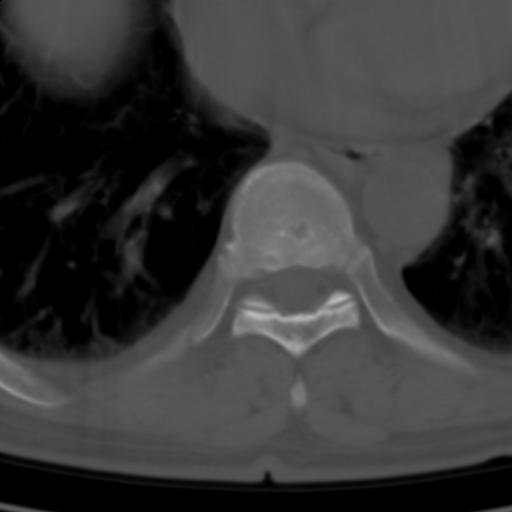

标题: CT25189:胸椎ct,请会诊!

既往食管癌,现行ct检查!

椎体退行性改变,食管癌。

支持中上段食道癌,椎体轻度退变,必要时做ect。

支持中上段食道癌,椎体轻度退变。